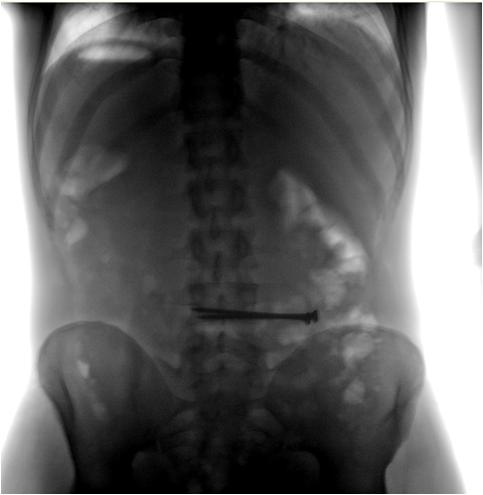

Пример сырого снимка и после обработки, на самом деле оригинальный фаил весит около 14,5 мб и его нужно смотреть на рентгенологическом мониторе, а после конвертации в бытовые форматы и сжатия информативность в разы уменьшается.

Ну, слева изображение, которое анализу не подлежит.

Но, Вы-то понимаете, что "цифровые изображения", даже после математической обработки представляют из себя изображения неудовлетворительного качества?